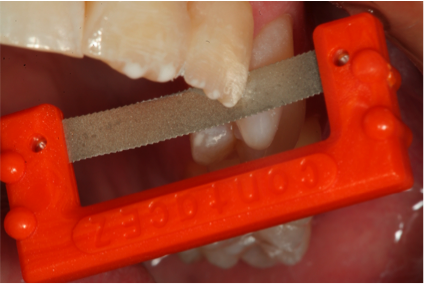

Prior to placement of the bulk-fill flowable resin, the clinician may apply either a self-etch or total-etch bonding adhesive to the enamel and dentin surfaces, which are then light-cured. The dentin replacement is achieved using increments of up to 4 mm of one of the bulk-fill flowable materials (eg, Surefil® SDR®; DENTSPLY Caulk; Venus® Bulk Fill, Heraeus Kulzer; Filtek™ Bulk Fill, 3M ESPE, solutions.3m.com; X-tra Base, VOCO, www.voco.com; Beautifil-Bulk Flow, Shofu, www.shofu.com) and light-cured, followed by placement of a nanohybrid enamel layer (eg, Venus® Pearl, Heraeus Kulzer). Each layer is polymerized, then finished and polished. It is common to have large overhangs using conventional matrices rather than sectional matrices. Interproximal finishing is achieved using specially designed diamond strips, which can also be used to clear the contact when teeth are accidentally bonded together without affecting the contact of restorative material (Figure 10).17

Figure 10. Diamond strips used for interproximal finishing can also be used to clear the contact when teeth are accidentally bonded together.

Figure 10